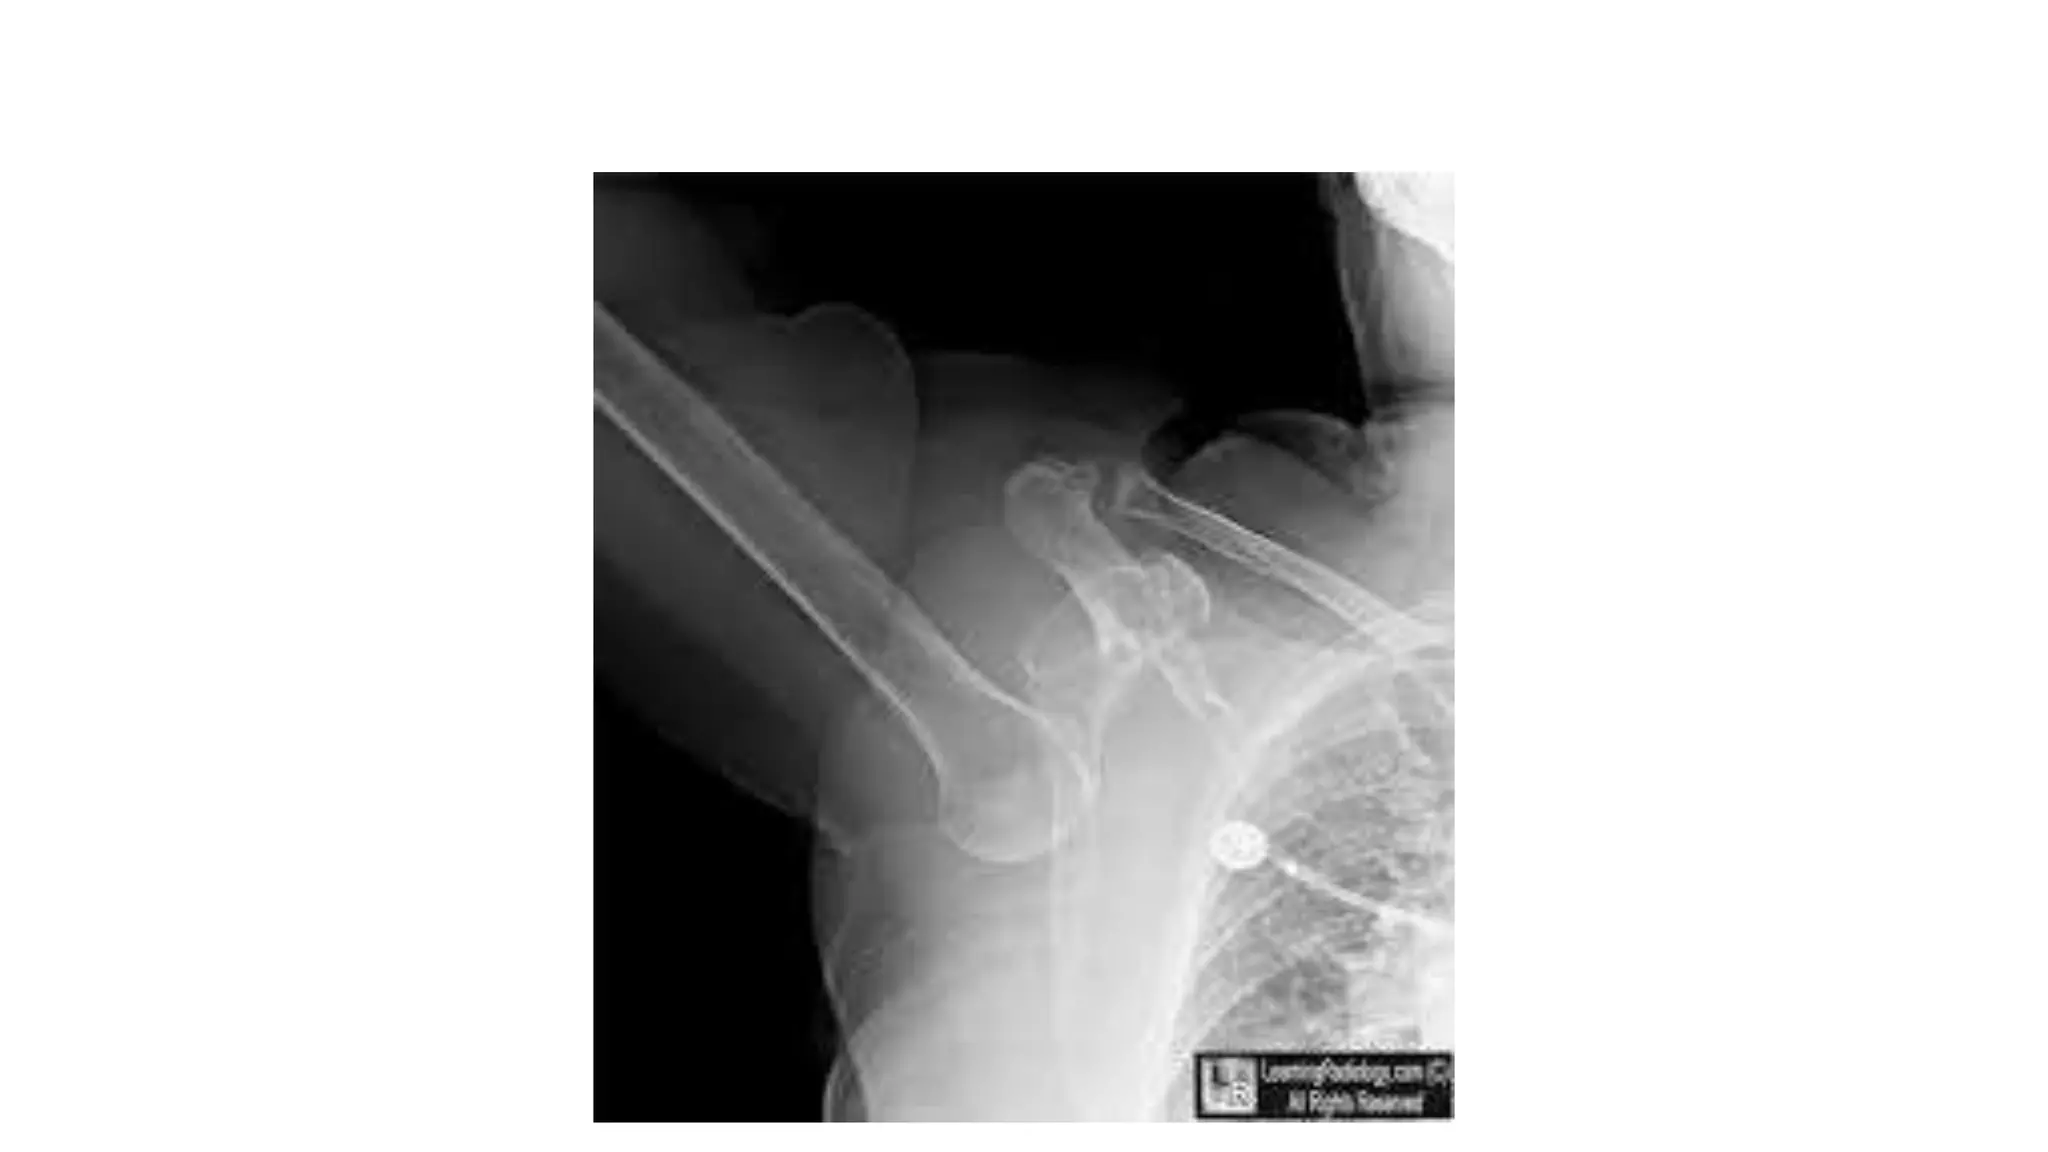

Imaging

Radiography

• AP :- unreliable and cannot be exclude posterior dislocation.

may show lightbulb sign.

• Axillary lateral :- best view to demonstrate a dislocation.

• Velpeau view :- if patient is unable to abduct arm for axillary view.

AP view

Axillary view

Velpeau view